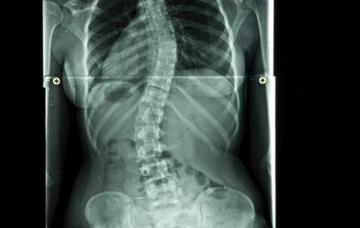

La escoliosis es una desviación lateral de más de 10º de la columna vertebral, con alteraciones anatómicas que el paciente no puede corregir voluntariamente.

En el diagnóstico de la escoliosis hay que determinar si se trata de una deformidad postural o estructural, mediante diversas pruebas y series radiológicas.